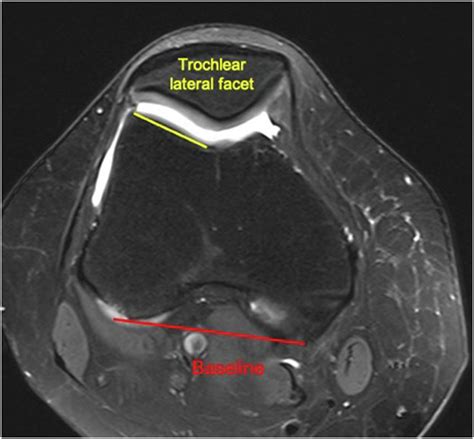

The patella is designed to glide vertically within the femoral groove (the trochlear groove) of the femur. When the mechanics of the knee are balanced, this movement is seamless. However, lateral patellar tilt happens when the soft tissues—specifically the lateral retinaculum on the outside of the knee—become too tight, while the muscles on the inside are relatively weak. This imbalance causes the kneecap to tip outward, increasing pressure on the lateral facet of the patella. Over time, this abnormal tracking can lead to cartilage wear, inflammation, and chronic pain, a condition often categorized under patellofemoral pain syndrome (PFPS).

• lateral patellar tilt angle